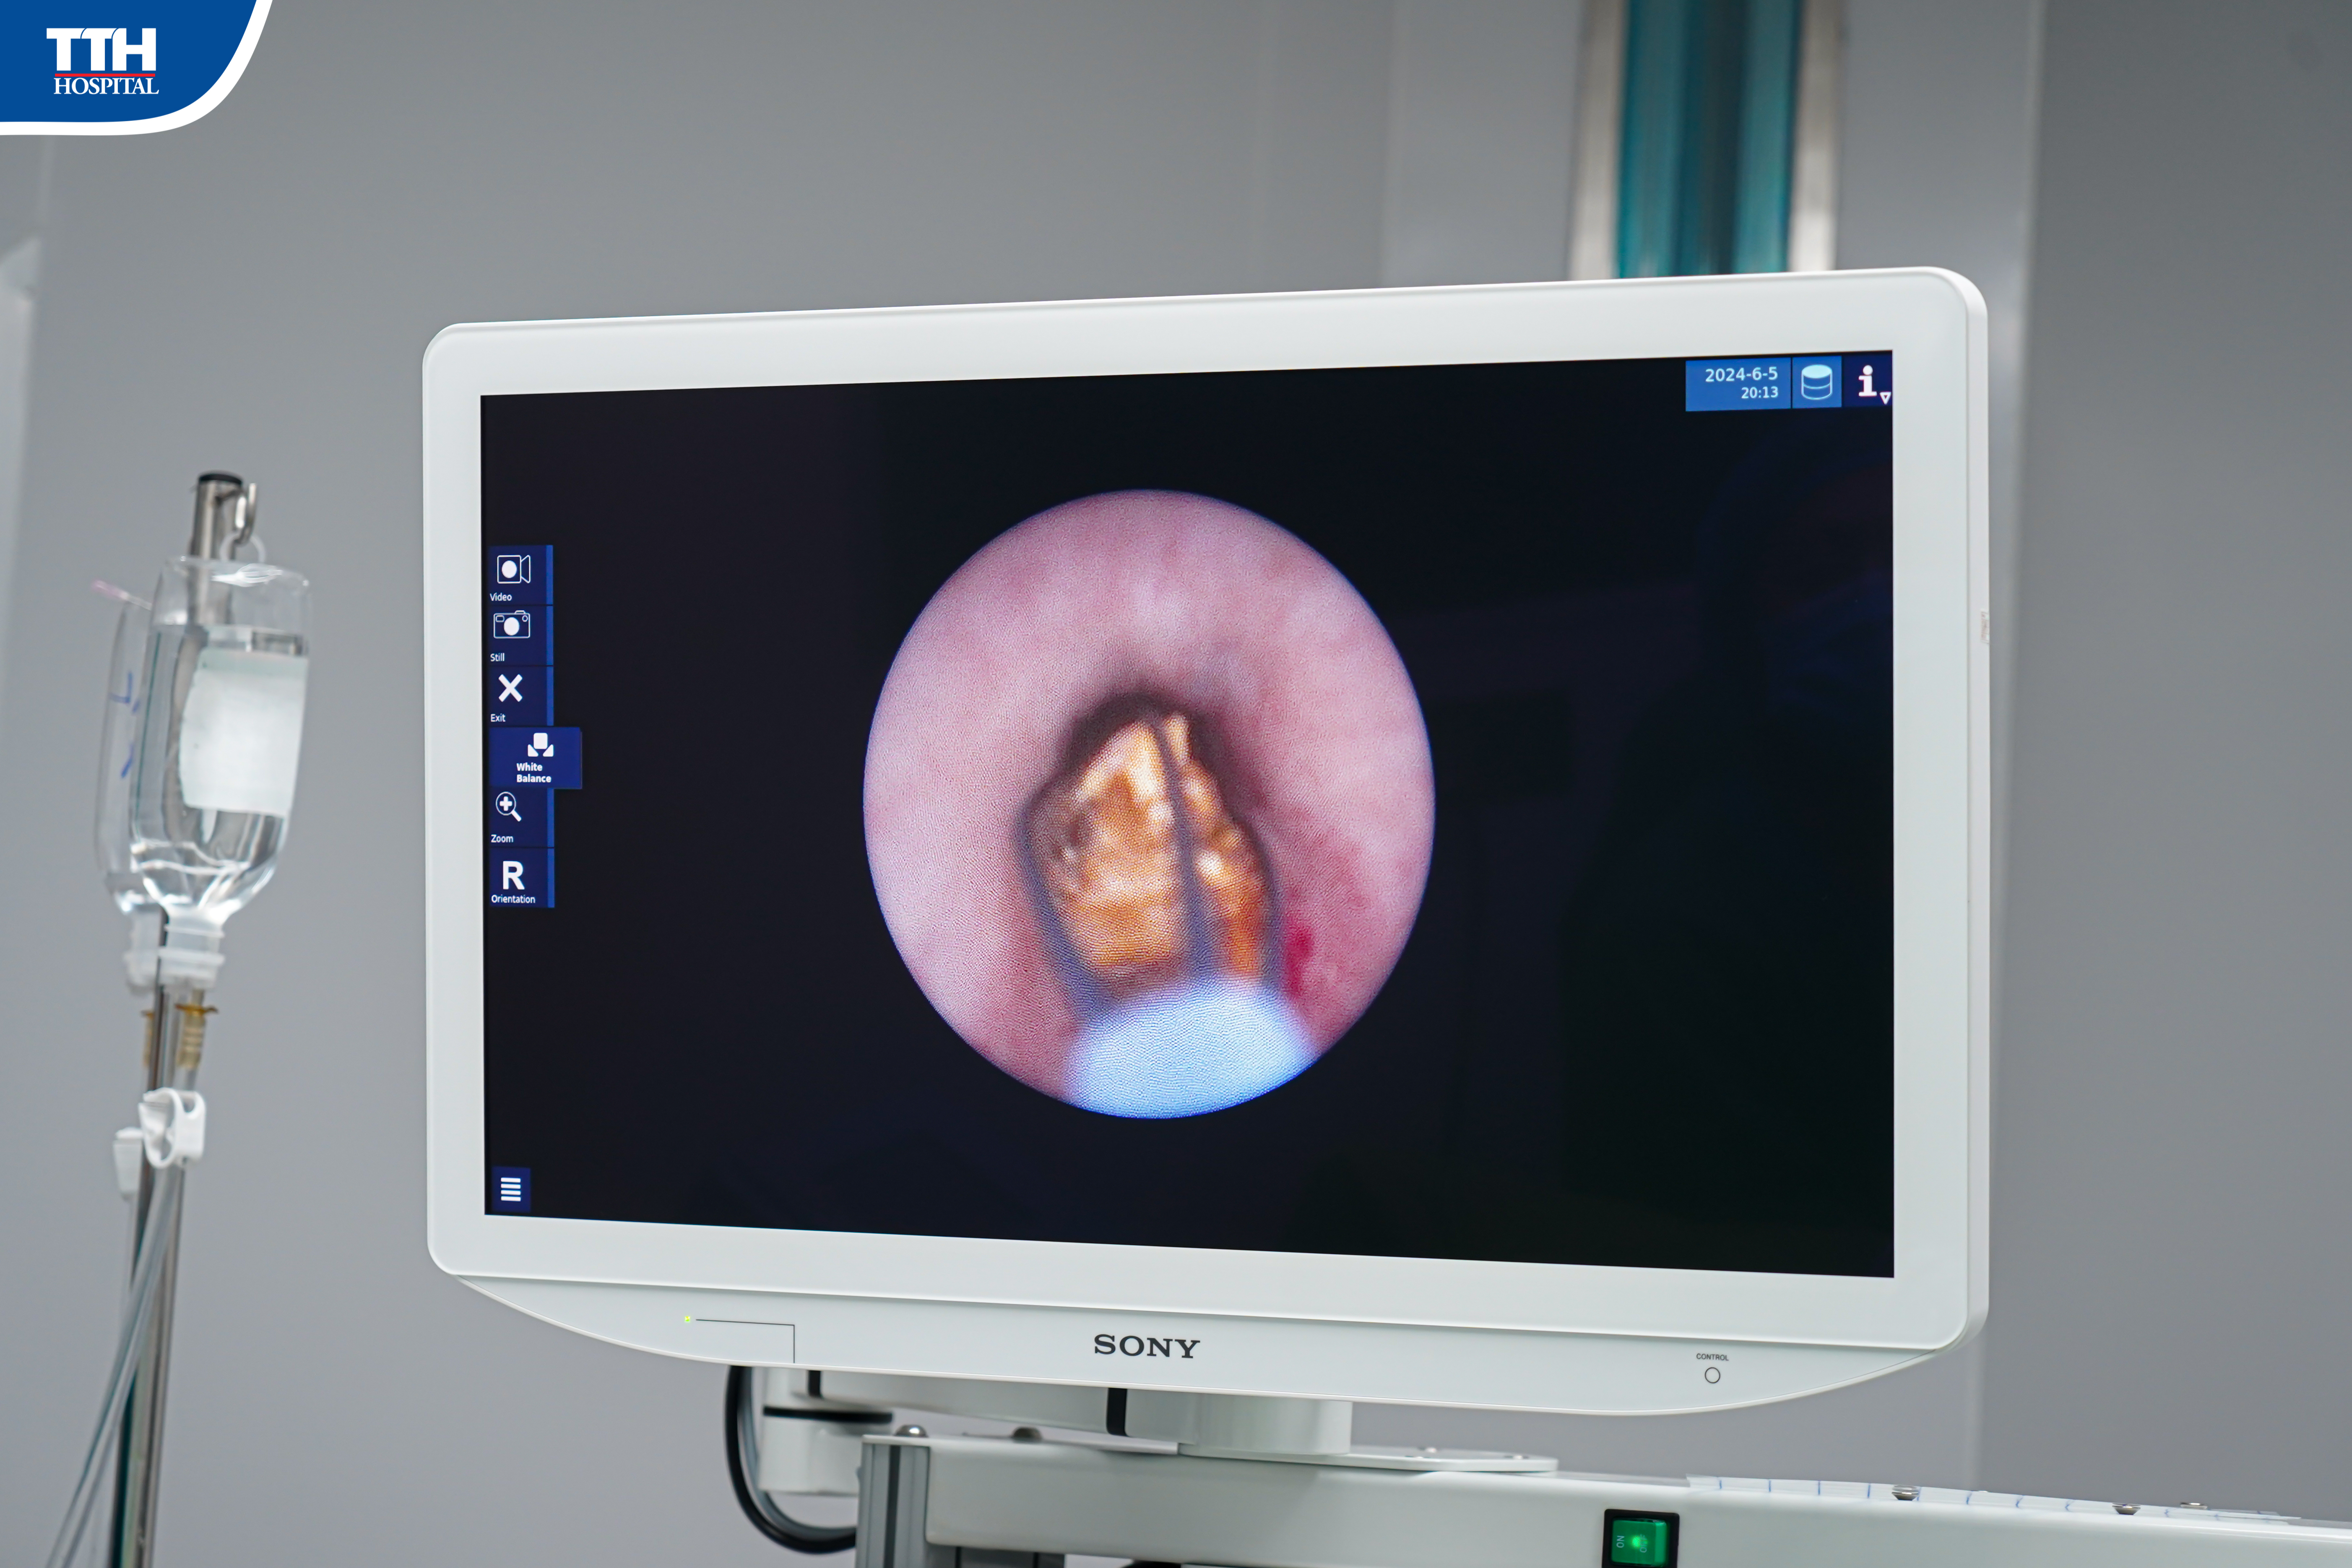

Tán sỏi ống soi mềm là một trong những kỹ thuật hiện đại nhất, được áp dụng tại các bệnh viện lớn có trang bị đầy đủ trang thiết bị hiện đại và yêu cầu trình độ bác sĩ cao. Kỹ thuật này được thực hiện bằng việc đưa ống soi mềm qua đường tiểu lên niệu quản - bể thận, vào tận các đài thận và tán vụn sỏi bằng tia laser. Đây là điều mà các kỹ thuật nội soi khác không làm được. Mọi thao tác của kỹ thuật đều thực hiện qua đường tự nhiên, không để lại sẹo, giúp bảo tồn tối đa chức năng thận, trị sỏi triệt để, an toàn cao, người bệnh phục hồi nhanh, ra viện sớm.Nhằm mục đích cho người dân tiếp cận với phương pháp kỹ thuật mới, hiện đại, nâng cao chất lượng điều trị và chất lượng sau điều trị, Bệnh viện Đa khoa TTH Quảng Bình đã triển khai kỹ thuật nội soi tán sỏi ống mềm thành công cho nhiều bệnh nhân.

Vừa qua, Khoa ngoại Tổng hợp Bệnh viện Đa khoa TTH Quảng Bình vừa phẫu thuật tán sỏi ống mềm thành công cho bệnh nhân. Theo đó, bệnh nhân B.N.D (39 tuổi, Lệ Thủy) đến bệnh viện thăm khám trong tình trạng đau hông lưng trái trước đó 1 tuần. Bệnh nhân được bác sĩ chỉ định thực hiện các chỉ định cận lâm sàng cần thiết, kết quả chụp cắt lớp vi tính cho thấy hình ảnh 2 viên sỏi ở niệu quản trái ⅓ trên kích thước 15x5mm gây giãn ứ nước đoạn niệu quản trên, giãn ứ nước đài bể thận (T) độ II, kèm sỏi đài dưới thận trái. Sau khi thăm khám cũng như dựa vào các kết quả cận lâm sàng, nhận thấy tán sỏi bằng ống mềm là phương án phẫu thuật an toàn và phù hợp cho bệnh nhân. Do vậy, bác sĩ đã chỉ định phẫu thuật nội soi tán sỏi ngược dòng bằng ống soi mềm.

ThS. BSNT Võ Trường Giang - Phó Trưởng khoa Ngoại Tổng hợp, Bệnh viện Đa khoa TTH Quảng Bình - người trực tiếp phẫu thuật cho bệnh nhân cho biết: “Bệnh nhân có nhiều viên sỏi có kích thước nhỏ ở đài bể thận, kèm 2 viên sỏi rơi xuống niệu quản, nếu sử dụng các phương pháp khác thì nguy cơ sót sỏi rất cao. Nhưng đối với phương pháp tán sỏi bằng ống mềm thì có thể quan sát được toàn bộ đài bể thận, tìm ra các viên sỏi nằm sâu trong thận và xử lý chúng. Các viên sỏi sẽ được tán nhỏ bằng laser, tiếp sau đó chúng sẽ được hút hoặc trôi ra ngoài theo đường bệnh nhân đi tiểu.”